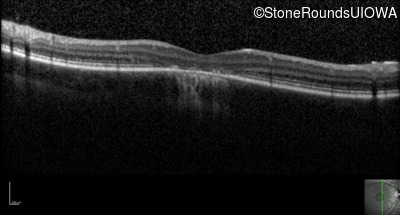

Optical Coherence Tomography - Left - 20/125 sc

Exemplar / OCT Stack

OCT Stack